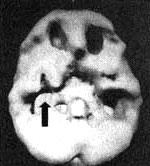

Меня же подобная бесстрастность, которую демонстрирует наша страна в этом вопросе, не перестает удивлять. В 1996 году в моем родном штате Калифорния был принят закон, разрешающий использование марихуаны в лечебных целях. Мне кажется, что многие неверно поняли Предложение 215. Они, наверное, думали, что, голосуя за это предложение, дают возможность пациентам, умирающим от рака, употреблять марихуану, чтобы облегчать боль и повышать аппетит. На самом же деле они получили закон, позволяющий врачу выписывать рецепт на марихуану при таких состояниях, как тревожность, стресс, плохое настроение или раздражительность. На мой взгляд, самый серьезный вред от этого закона состоит в том, что люди перестали считать марихуану опасной. Подростки рассказывают мне, что марихуана — всего лишь лекарство. Специалист по наркотическим зависимостям Марк Голд выразился кратко: «Чем легче люди относятся к наркотику, тем больше его употребляют». Методика SPECT использовалась для исследования длительного и кратковременного воздействия марихуаны на головной мозг. Полученные результаты свидетельствуют о том, что по сравнению с контрольной группой, не употреблявшей марихуану, у тех, кто начал курить ее относительно недавно, отмечалось острое снижение кровообращения в тканях мозга, в то время как у «опытных» потребителей конопли наблюдалось общее снижение перфузии. Обследовав на SPECT многих курильщиков конопли, я заметил еще одну особенность, не отраженную в результатах предыдущих исследований: сниженную активность височных долей. Авторы исследований могли не заметить этого просто потому, что более старые аппараты SPECT дают изображения более низкого разрешения, чем современные. Я задумался: а не является ли наше открытие причиной часто наблюдающихся у курильщиков «травы» снижения памяти и мотивации? Я решил изучить воздействие марихуаны на головной мозг, сравнивая хронических курильщиков «травы», которым был к тому же диагностирован СДВ, с пациентами с СДВ, никогда не курившими марихуану. Такое решение было принято по нескольким соображениям: во-первых, на изображениях мозга у пациентов с СДВ не было поражения височных долей. При этом, если контрольная группа будет представлена пациентами с таким же диагнозом, а не просто психически здоровыми людьми, это повышает чистоту эксперимента, так как обычно у курильщиков марихуаны существует большое количество дополнительных характерных диагнозов. При этом сравнение результатов у групп с одинаковым основным диагнозом позволило бы получить и другие интересные результаты. Наконец, 52 % людей с СДВ злоупотребляют наркотиками, алкоголем или другими веществами и чаще всего — марихуаной. Последствия злоупотребления марихуаной ![]() Трехмерное изображение поверхности, вид снизу. Мозг 16-летнего молодого человека, употреблявшего марихуану каждый день на протяжении двух лет; обратите внимание на многочисленные области выраженного снижения активности, особенно в височных долях (стрелки). ![]() Трехмерное изображение поверхности, вид снизу. Мозг 44-летнего мужчины, употреблявшего марихуану каждый день на протяжении двенадцати лет; обратите внимание на выраженное снижение активности в нижней поверхности мозга. ![]() Трехмерное изображение поверхности, вид снизу. Мозг 32-летней женщины, употреблявшей марихуану по выходным на протяжении двенадцати лет: обратите внимание на снижение активности в средней части височных долей. Я сравнил результаты, полученные у тридцати подростков и взрослых, куривших марихуану на протяжении не менее одного года и не реже раза в неделю, с результатами десяти пациентов контрольной группы. При этом мы старались обеспечить соответствие испытуемых по возрасту, полу и доминирующему полушарию мозга. Если верить собранному анамнезу, пациенты группы «марихуана/СДВ» употребляли главным образом марихуану, а в течение 12 месяцев перед обследованием — только марихуану. Среди них никто не употреблял алкоголя в значительных дозах (под значительной дозой мы подразумевали более 3 унций (80 г) крепких спиртных напитков или шести банок пива в неделю). Интервал между обследованием и последним эпизодом употребления марихуаны составлял от одного до шести месяцев. Если пациент удовлетворял диагностическим критериям алкогольной или иной наркотической зависимости, он не участвовал в этом исследовании. До опыта испытуемые употребляли марихуану с разной частотой — от раза до семи раз в неделю, а стаж употребления варьировался от одного года до 22 лет. Во время обследования испытуемые не принимали никаких медицинских препаратов, а те из них, кому для коррекции СДВ ранее назначались медицинские стимуляторы, к моменту обследования не принимали это лекарство минимум неделю. Единственным нарушением, выявленным у пациентов контрольной группы (СДВ), оказалась сниженная активность префронтальной коры (в 8 случаях из 10). Приблизительно такая же частота случаев сниженной активности префронтальной коры наблюдалась и в основной группе (в 25 из 30 случаев — 83 %). Однако в этой группе поражение префронтальной коры носило гораздо более выраженный характер. Кроме того, у 24 пациентов основной группы было выявлено снижение активности височных долей: у пяти из них (21 %) степень поражения оценивалась как тяжелая, у семи (29 %) — средней тяжести и у 12 (50 %) — как легкая. Тяжелая и средняя степень поражения височных долей была выявлена у тех, кто в течение последнего года курил марихуану минимум четыре раза в неделю. Однако длительность употребления наркотика в данном случае роли не играла. Один из наиболее тяжелых случаев нарушения перфузии височных долей мы обнаружили у подростка, который на протяжении двух лет курил марихуану ежедневно. У четырех пациентов был выявлен синдром отсутствия мотивации (ярко выраженное отсутствие интереса, мотивации и энергии). У всех четверых наблюдалась сниженная перфузия в височных долях, причем в трех случаях нарушение перфузии было классифицировано как тяжелое и в одном средней тяжести. Результаты этого исследования подтвердили выводы, к которым пришли авторы предыдущих работ: частое употребление марихуаны на протяжении длительного периода времени может отрицательно сказываться на мозговом кровообращении. Если предыдущие исследования выявили общее снижение активности мозга, то нам удалось обнаружить еще и очаговое поражение височных долей (очевидно, за счет использования нами более совершенной аппаратуры). Нарушение активности височных долей вызывает проблемы с памятью, обучением и мотивацией — стандартный набор жалоб, который можно услышать от подростков (или хотя бы от их родителей) и взрослых, употребляющих марихуану на протяжении нескольких лет. У подростка, курившего марихуану каждый день на протяжении двух лет, был выявлен один из самых тяжелых случаев нарушения работы височных долей. Его симптомы соответствовали картине синдрома отсутствия мотивации, а сам он в 11-м классе бросил школу. |